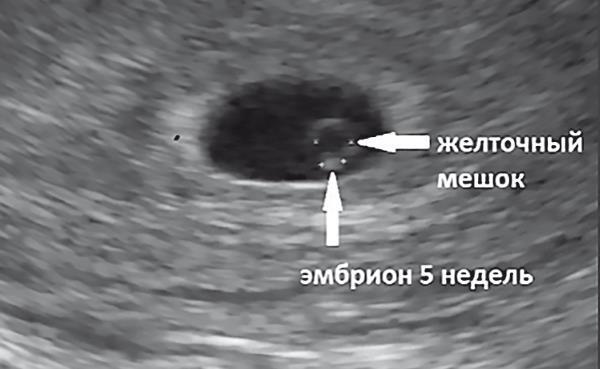

Известно, что жизнь ребенка начинается не с момента рождения, а с момента оплодотворения яйцеклетки (рис. 1.6).

12 недель – максимально допустимый срок, когда искусственное прерывание беременности (аборт) все еще официально разрешено (рис. 1.7).

Рис. 1.6. Ультразвуковое исследование: эмбрион 5 недель